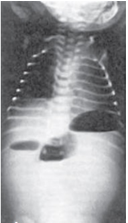

【111-1 醫學(四) 第11題】新生兒出生1天後開始出現嘔吐症狀,嘔吐物含膽汁。身體診察發現腹部平坦,腹部X光片(如附圖)顯示中腹有3團腸氣而其他部位無腸氣出現。下列何者為最可能之診斷?

詳解

破題關鍵

新生兒出現膽汁性嘔吐,加上腹部X光片顯示「三團腸氣」且遠端無腸氣,這是判斷小腸近端閉鎖的經典影像學表現。

選項拆解

-A:錯在胃幽門狹窄通常是「非膽汁性」嘔吐,且X光片不會出現多個氣泡,而是胃部擴張。通常發生在出生後2-6週。